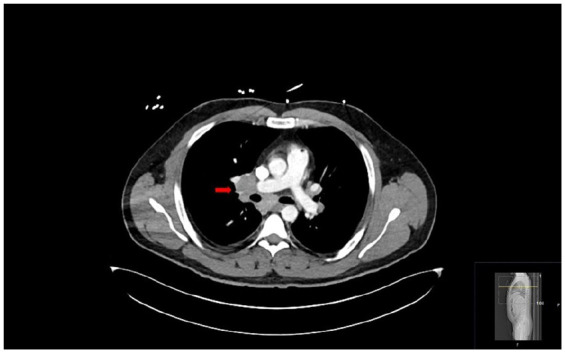

Löfgren's syndrome is an acute, self-limiting variant of sarcoidosis, typically presenting with erythema nodosum, bilateral hilar lymphadenopathy, and acute arthritis or periarthritis-most commonly involving the ankles. Its clinical overlap with other inflammatory conditions can pose a diagnostic challenge. We describe a 34-year-old male with no prior medical history who presented with bilateral ankle and foot pain, erythema, and swelling, initially diagnosed as cellulitis based on imaging findings. He has no response to broad-spectrum antibiotics. During his further hospital stay, he developed polyarthritis. Laboratory evaluation revealed neutrophilic leukocytosis, elevated inflammatory markers, and a normal serum angiotensin-converting enzyme level. Imaging showed bilateral hilar lymphadenopathy and intra-abdominal adenopathy. Bronchoscopy with bronchoalveolar lavage revealed an elevated CD4:CD8 ratio (5.0), and endobronchial ultrasound-guided transbronchial needle aspiration confirmed noncaseating granulomas. Infectious, autoimmune, and malignant causes were excluded. Based on clinical features and histology, a diagnosis of Löfgren's syndrome was established. Nonsteroidal anti-inflammatory drug therapy led to rapid clinical improvement, and antibiotics were discontinued. Löfgren's syndrome should be considered in patients presenting with bilateral lower extremity erythema and swelling unresponsive to antibiotics, especially when accompanied by systemic symptoms. Early thoracic imaging and consideration of sarcoidosis in the differential diagnosis can prevent misdiagnosis and unnecessary treatment.

Abstract Image